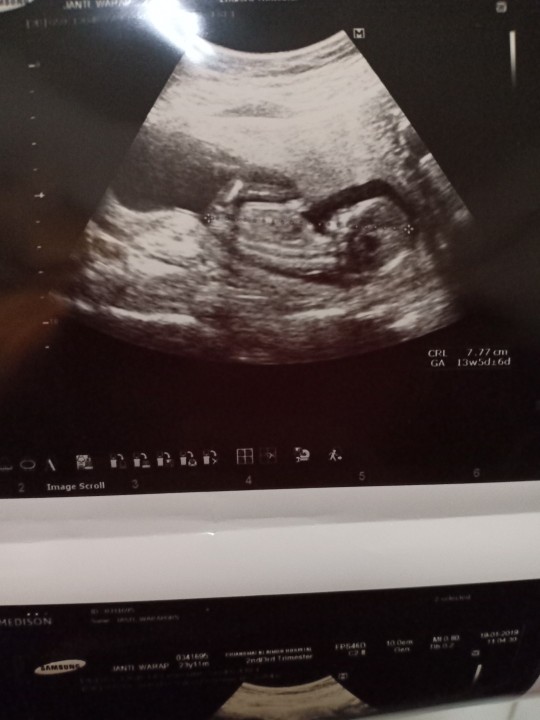

ช่วง 13 วีคค่ะ